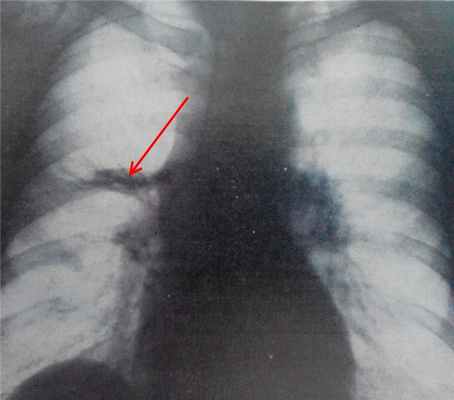

(а) При рентгенографии органов грудной клетки в ПП проекции определяется объемное уменьшение левого легкого и ателектаз нижней его доли. Следует отметить наличие бронхоэктазов в ателектазированной доле, что свидетельствует о хроническом ее коллабировании.

(б) У этого же пациента при КТ с контрастным усилением в нижней доле левого легкого визуализируется эндобронхиальный узелок пониженной плотности с макроскопическими жировыми включениями. При хирургическом вмешательстве была выявлена эндобронхиальная гамартома. В дифференциальный ряд также может быть включена и эндобронхиальная липома, однако при КТ она характеризуется наличием только участков жировой плотности. (а) При прицельной рентгенографии органов грудной клетки в ПП проекции в верхней доле левого легкого определяются гетерогенные затемнения, а также признаки объемного уменьшения данной доли и наличия бронхоэктазов.

(б) У этого же пациента при КТ с контрастным усилением визуализируется обструкция проксимальных отделов левого верхнедолевого бронха узелком. Следует отметить наличие макроскопических жировых включений в структуре данного образования, что типично для гамартомы и липомы. У пациентов с эндобронхиальной гамартомой при рентгенографии органов грудной клетки чаще всего выявляют ателектаз, участки консолидации легочной ткани и бронхоэктазы.